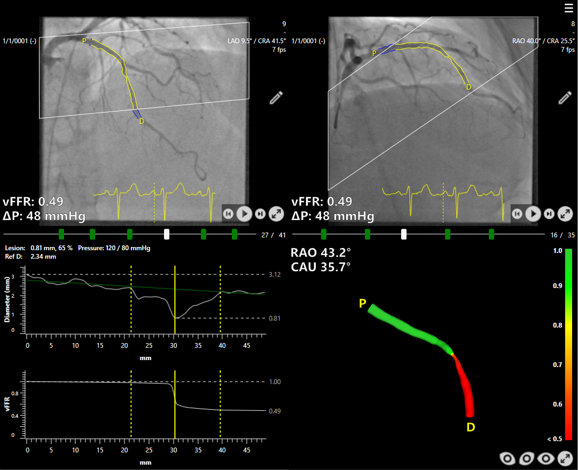

Results from the FAST III study, presented at the American College of Cardiology Congress and published in the New England Journal of Medicine, confirm that angiography-based vessel fractional flow reserve (vFFR) can guide coronary interventions as effectively as traditional pressure wire-based methods.

The vFFR approach uses software to calculate blood flow restriction from angiographic images, removing the need for pressure wires and pharmacologically induced hyperemia. This may reduce patient discomfort and procedural complexity.

According to the study findings, the method achieved comparable clinical outcomes, supporting its use as an alternative in patients with intermediate coronary artery stenosis.